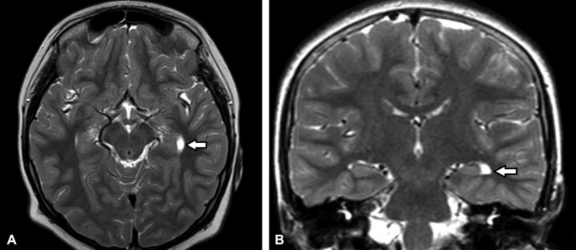

Constituyen variantes anatómicas que se presentan en la línea media derivando de alteraciones del desarrollo del septum pellucidum (SP).7 En TC y RM se los aprecia con densidad o señal similar al LCR (►Figs. 1, 2, 3).7

Resonancia magnética (RM) de cerebro, corte axial ponderado en T2: la flecha señala al cavum septum pellucidum (CSP) entre las astas frontales de los ventrículos laterales.

RM de cerebro corte axial ponderada en T2: se evidencia una cavidad interpuesta entre los ventrículos laterales (asterisco). Corresponde a cavum vergae (CV) asociado a CSP.

RM de cerebro, corte axial ponderado en T1. Se señala (flecha) la presencia de una cavidad triangular cefálica al trígono, compatible con cavum del velo interpósito (CVI).